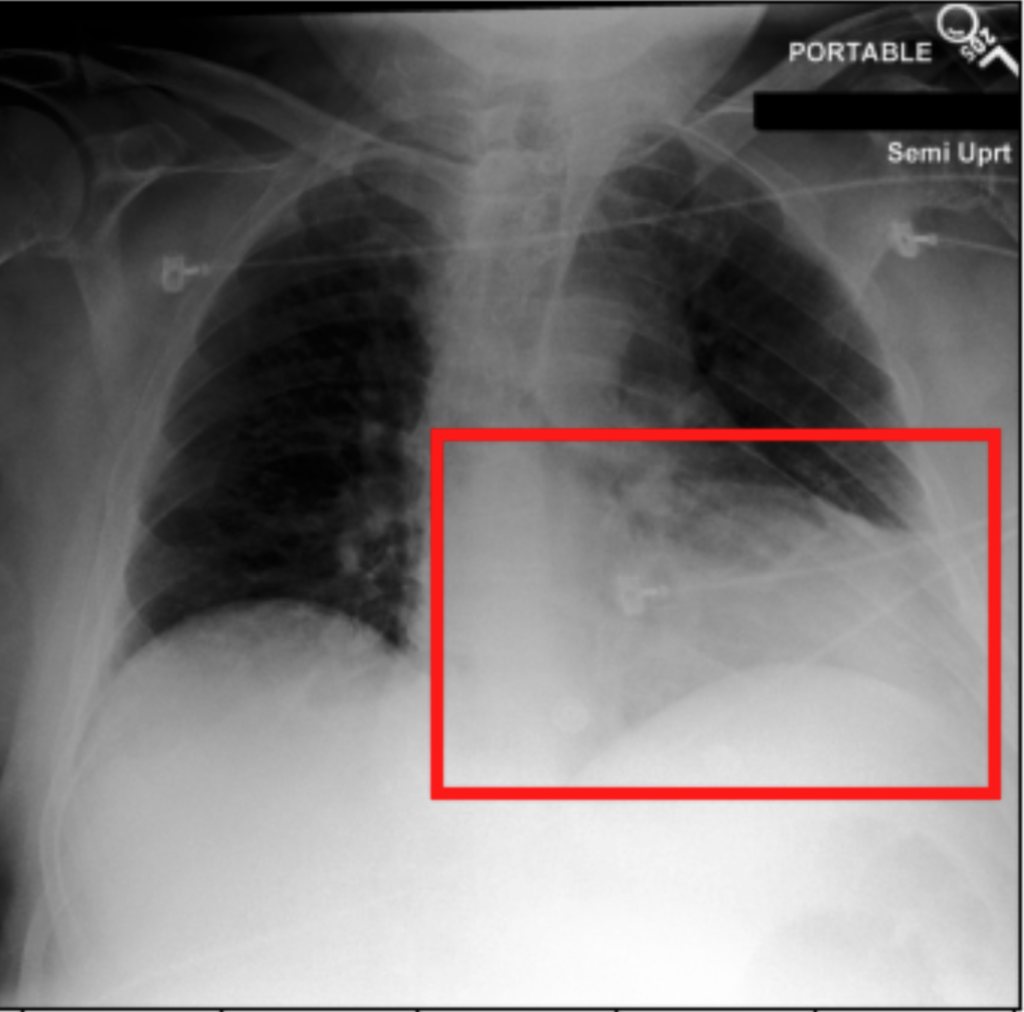

4.3.3 Visual grounding

In this section, we evaluate RadVLM’s visual grounding capabilities, which could help clinicians localize specific regions or pathologies on a CXR. This is particularly useful once a pathology has already been identified – either by a radiologist’s input or through our previously described AI tasks – since it allows one to pinpoint exactly where the abnormality appears on the image.

We report performance metrics for the three main grounding tasks RadVLM was trained on: anatomical grounding using the Chest Imagenome test set, abnormality grounding using the VinDr-CXR test set, and phrase grounding using the MS-CXR test set (Table 1). For each task, we use mean Average Precision (mAP) as our primary evaluation metric.

As mentioned in Table 2, some of the CXR-specific VLMs already have grounding capabilities. CheXagent was trained to handle both abnormality and phrase grounding tasks, while MAIRA-2 – originally trained to produce radiology reports with grounded observations – is also capable of predicting bounding box coordinates when provided with input text. After retrieving each model’s instruction template for generating bounding box coordinates (Appendix 1-Table 2), we evaluated both CheXagent and MAIRA-2 on all three grounding tasks performed by RadVLM.

Our results show that RadVLM performs well at localizing anatomical regions (e.g., “right lung”, “aortic arch”, illustrated in Figure 5a), achieving a mAP of 85.8 %, by far surpassing the other CXR grounding models (Table 4). This advantage is partly explained by including the Chest Imagenome dataset (and thus the anatomical grounding task) in the training set, which CheXagent and MAIRA-2 did not leverage. However, it remains a key feature for any grounding model to possess a fine-grained understanding of CXR anatomy.

For the abnormality grounding task, RadVLM is less consistent (Figure 5b), likely due to higher sparsity of abnormality locations and labels, yet it still achieves best performance (Table 4). For the phrase grounding task, while MAIRA-2 and CheXagent demonstrate great performance, RadVLM surpasses them with a mAP of 81.8% (Table 4), presumably benefiting from the newly released PadChest-GR dataset (Castro et al.,, 2024) used for training.

Overall, these results show that our instruction tuning strategy for visual grounding (covering three essential tasks), combined to a modern VLM backbone, offers a promising avenue to help clinicians localize anatomical and pathological features during a CXR exam. Furthermore, providing fine-grained details within an LLM-generated output may also enhance the ability to answer grounded questions in a multi-turn setting, as we explore next.

a. Anatomical grounding

silhouette

junction

structures

lung

abdomen

mediastinum

arch

b. Abnormality grounding

thickening

fibrosis

enlargement

lung disease

| Anatomical grounding | Abnormality grounding | Phrase grounding | |

| CheXagent | 6.2 | 26.0 | 69.7 |

| MAIRA-2 | 19.8 | 11.3 | 80.1 |

| RadVLM | 85.8 | 34.6 | 81.8 |